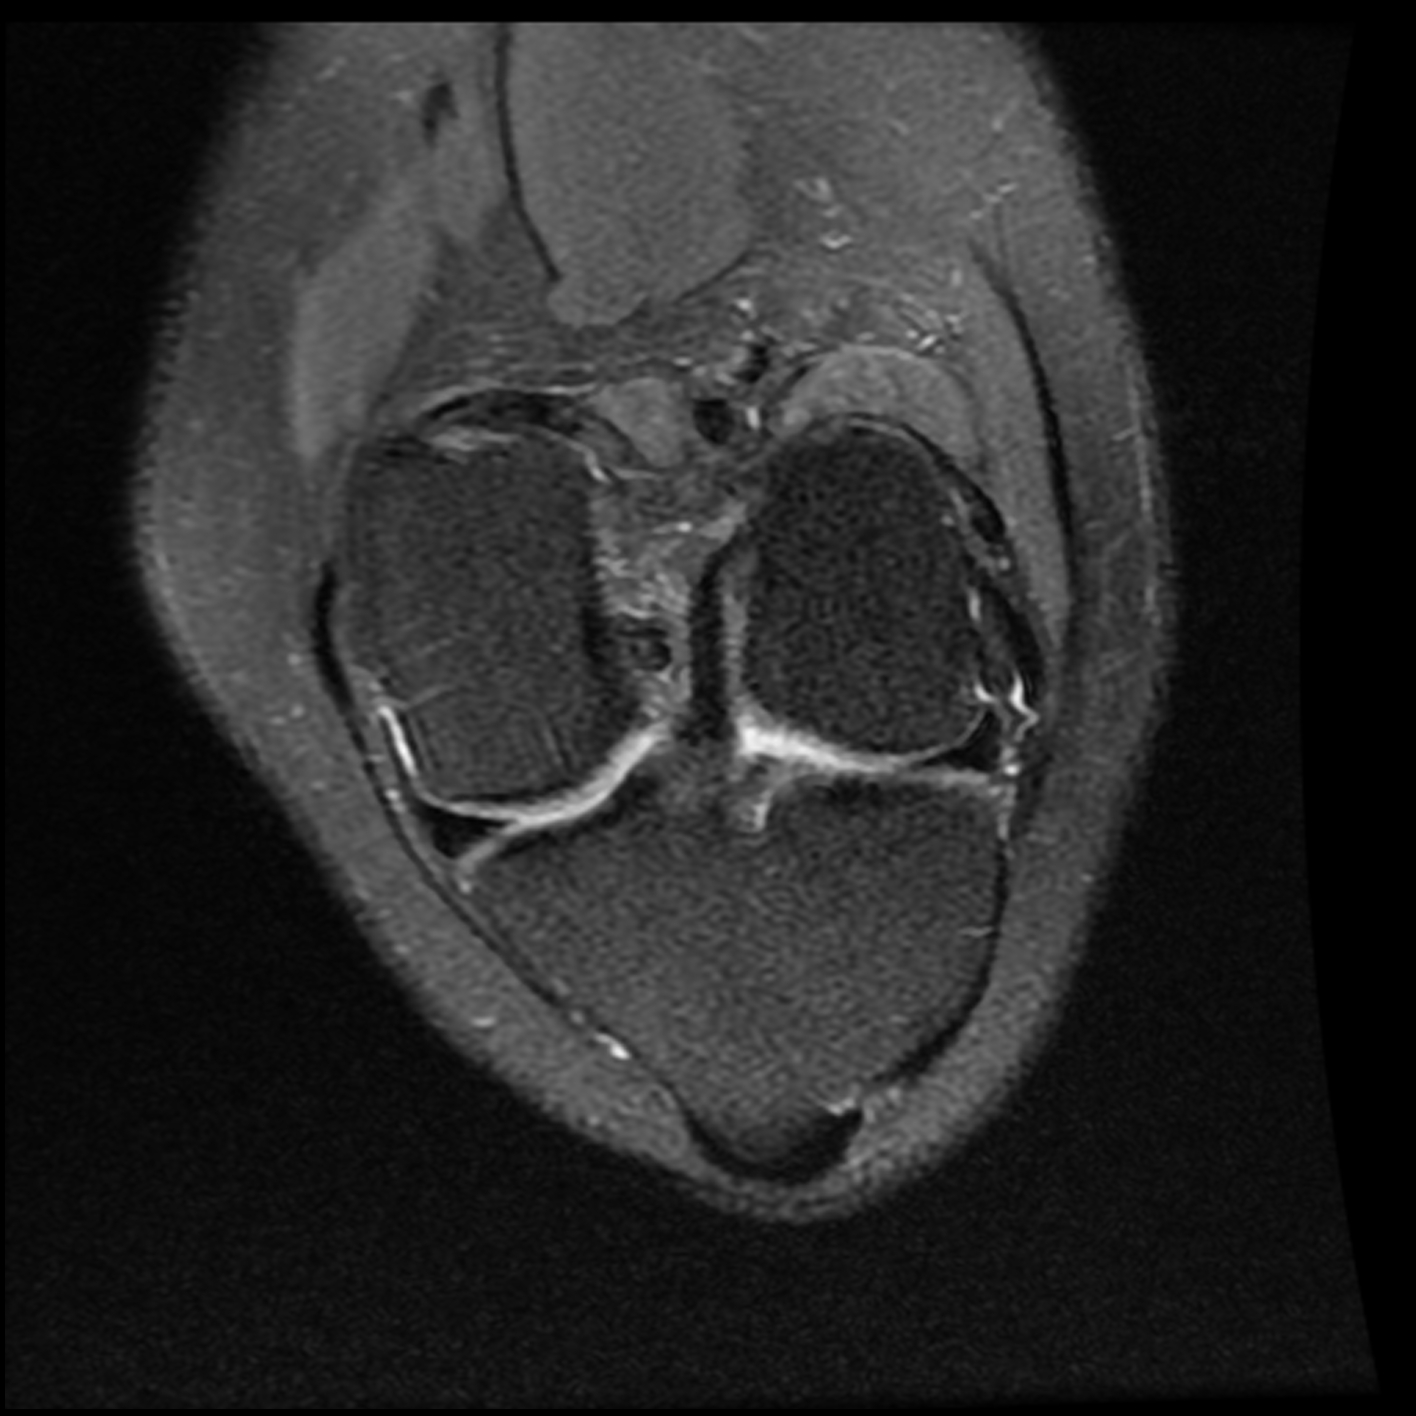

June 2020 MRI

IMPRESSION

- Healed femoral-sided ACL tear with partial attenuation of the proximal ACL fibers.

- Progressive healing of horizontal oblique tear of the medial meniscus posterior horn.

- Chronic inferiorly displaced meniscal flap tear at the lateral meniscus posterior

horn-root junction, less conspicuous than on prior MR imaging. Resolution of previously

noted horizontal longitudinal tear of the body-posterior horn segments. - No new evidence of internal derangement. No acute osseous abnormality.